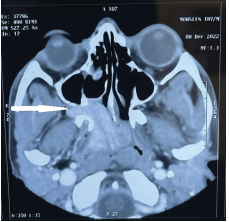

Computerised tomography image showing juvenile nasopharyngeal angiofibroma (white arrow) completely blocking the nasopharynx and extending throughright pterygo- maxillary fissure into the right infratemporal fossa